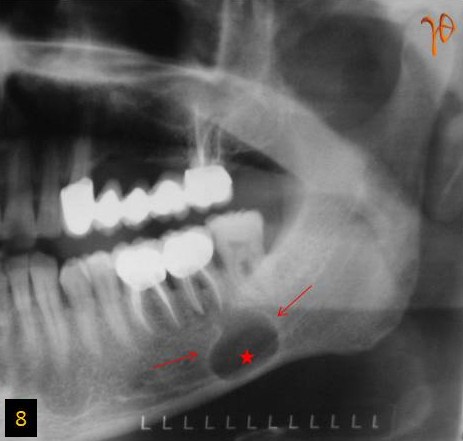

ΠΕΡΙΠΤΩΣΗ 4 8

Εικ. 8: Πανοραμική ακτινογραφία. Διαύγαση στο αριστερό σώμα της κάτω γνάθου (βέλη). Εμφανής η πορεία του αγγειονευρώδους δεματίου διαμέσου του κυστικού χώρου(άστρο).